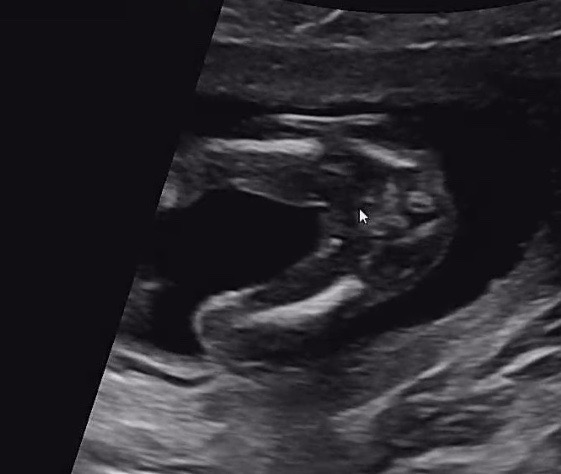

15주 가랑이 초음파 봐주세용🥹

의사선생님도 딸 51% 인거같은데 애매하네요~ 라고만 하시구 4주뒤에 오라고 하셔서😭😭 이대로 성별을 모른채 4주를 견딜 자신이 없어요 ㅋㅋㅋㅋ 고수분들 성별 한번만 봐주세요😭